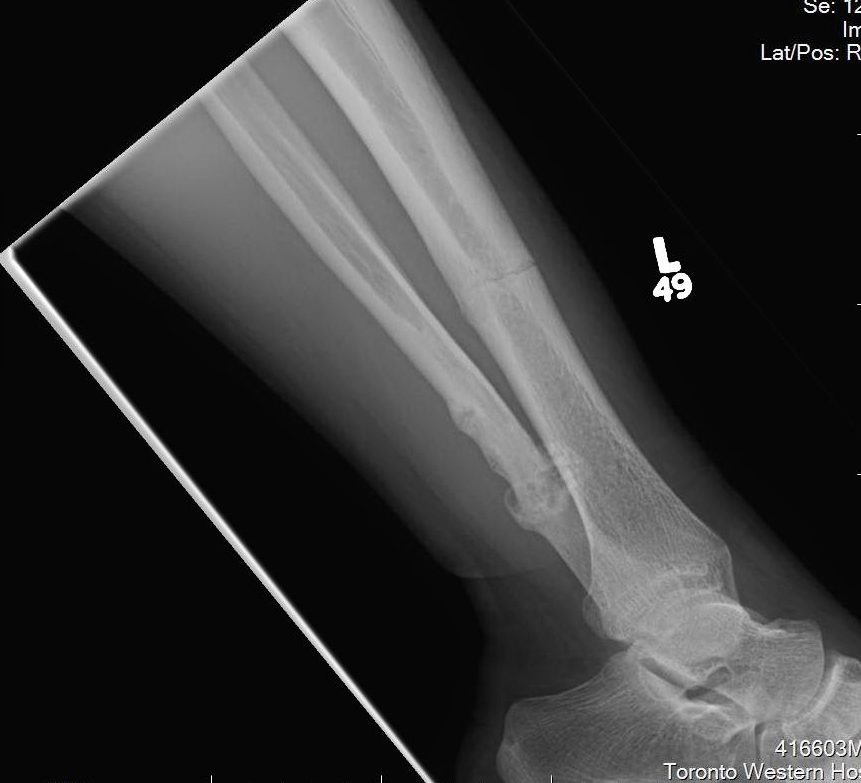

Xray

Cortical thickening

Look for "dreaded black line" - sign of fracture

Periosteal thickening with possible "dreaded black line"

Anterior cortical thickening with dreaded black line